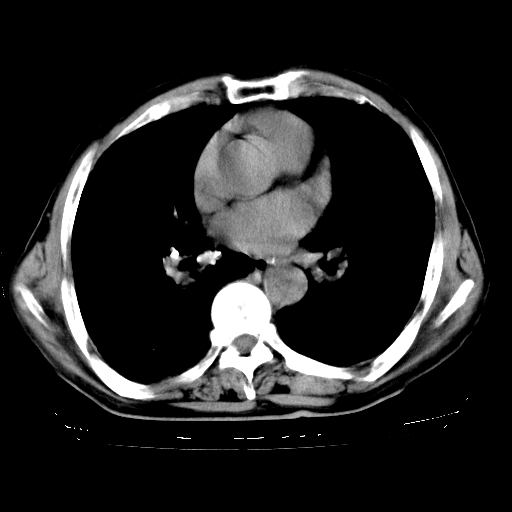

男,72岁,反复咳嗽、憋气一年余,有15年的煤矿井下工作史。

矽肺,冠心病

支持 尘肺,肺心病?-------15年的煤矿井下工作史,双上肺叫对称的片团结节影,内见斑状钙化,边缘见粗长毛刺影,肺纹理混乱,可见网状及磨玻璃样影,肺门纵膈见多个淋巴结钙化